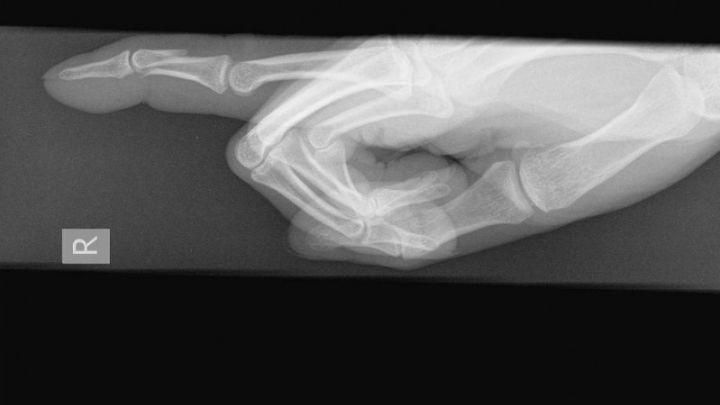

Roughly two weeks ago I smashed my finger while adventuring with friends. After 3 days of the swelling not going down  I decided to check myself into an urgent care where I was given the news that my finger was not only broken but it was broken in such a way that it required a referral to a specialist and possibly surgery.

Long story short the specialist confirmed my worst fears. I will need surgey to correct the finger and my surgery has been postponed until October 31st. For most this is a simple procedure that insurance would cover but unfortunetly through this whole ordeal I discovered my insurance policy had expired over 6 months ago. I've had to go through several different doctors as most have denied me due to being uninsured but I found a doctor who will do it for me but its going to cost $2,600 in total. I've already been paying upfront anywhere from $140-$250 for each visit I've gone to and am already more than ready to accept my fate of going into debt for the sake of getting my finger back to normal function.

With that being said I'd like to ask for help with paying for the surgery. While my injury is not life threatening it will affect the quality of my life as the finger is not only broken but slightly inverted causing very limited movement and if it heals like this my right hand would be disabled.